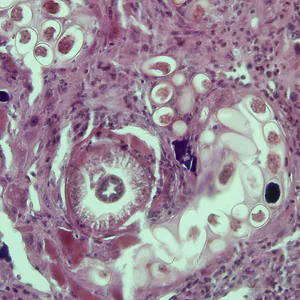

A 28-year-old man had loss of appetite, weight loss, and intermittent diarrhea approximately one week after attending a family reunion located on a farm in the mid-western U.S. He sought medical attention with his primary care provider who collected a stool specimen for ova and parasite (O&P) examination using a single-vial fixative system.